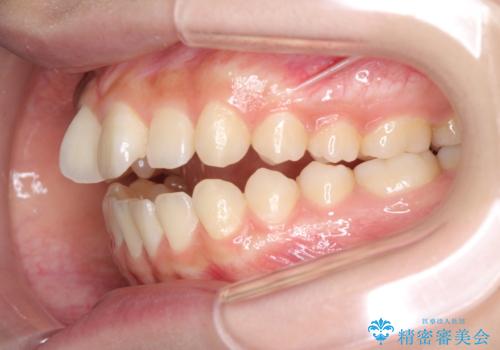

話しにくいオープンバイト ワイヤー装置による抜歯矯正治療

- 前歯のオープンバイトを気にして来院された患者様です。

上下前歯の前後位置が大きくずれていたため、上顎左右第一小臼歯2本を抜歯してワイヤー装置による矯正治療を行うこととしました。

オープンバイトの原因は舌の突出癖であり、癖が改善されないと治療経過に影響を及ぼすため、舌のトレーニングを指示しました。

なかなか癖が改善されず、トレーニングも断続的に行ったため、治療期間は長期化しました。